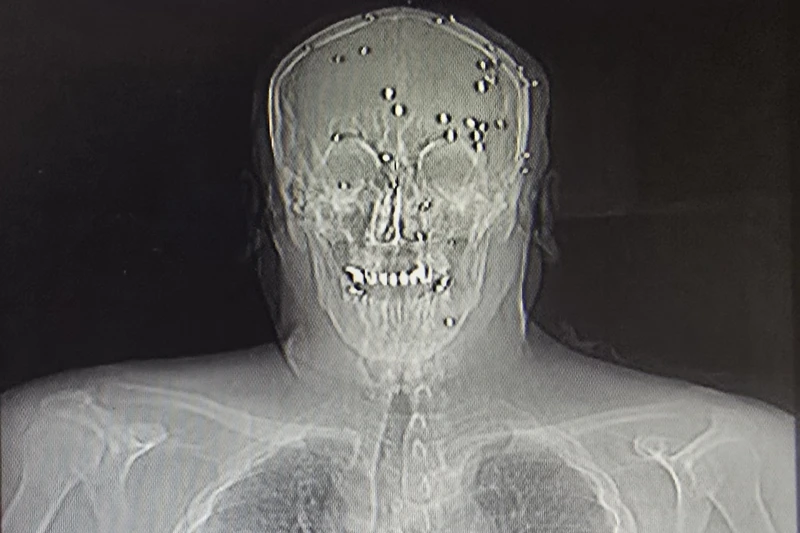

مع تدفّق محتجين جرحى مناهضين للحكومة إلى أحد المستشفيات الإيرانية خلال حملة القمع الشهر الماضي، سارع طبيب شاب إلى غرفة الطوارئ لمحاولة إنقاذ رجل في الأربعينيات من عمره أُصيب برصاصة في الرأس من مسافة قريبة.

فخلال أيام عدة في مطلع كانون الثاني/يناير، انتشر عناصر أمن بملابس مدنية داخل مستشفيات في مدن عدة كانت تستقبل آلاف الجرحى الذين أُصيبوا بعدما أطلقت قوات الأمن النار على حشود المحتجين في محاولة لقمع احتجاجات واسعة ضد النظام القائم منذ 47 عاماً. وبحسب روايات أطباء، قام هؤلاء العناصر بمراقبة العلاج الطبي وأحياناً عرقلته، كما أخافوا الطواقم، واحتجزوا بعض المصابين، ونقلوا جثامين قتلى. وتم توقيف عشرات الأطباء.

قال أطباء داخل إيران وخارجها إن مستوى العنف و”عسكرة” المرافق الصحية غير مسبوق، حتى في بلد شهد لعقود حملات قمع ومراقبة للمؤسسات العامة. وفي إحدى الحالات، أفاد شهود بأن قناصة تمركزوا على سطح مستشفى في مدينة جرجان شمال البلاد وأطلقوا النار باتجاه أشخاص كانوا يقتربون من المبنى.

ووثّق مركز حقوق الإنسان في إيران، ومقره أوسلو، شهادات متعددة تفيد بمنع تقديم الرعاية الطبية، ونزع أجهزة التنفس عن بعض المرضى، ومضايقة الأطباء واحتجاز محتجين.